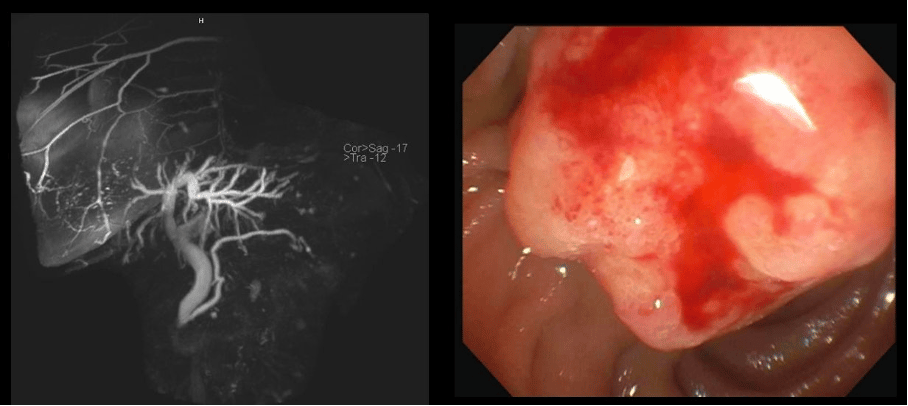

A female patient in her late 70’s with status post cholecystectomy and a history of breast cancer on anastrozole, which was stopped 1 month prior because of itching was found to have elevated liver tests (alkaline phosphatase up x 4, ALT up x 6, AST up x 4). MRCP showed dilated common bile duct to 11 mm with smooth tapering at ampulla of Vater. The patient was sent for EGD and endoscopic ultrasound (EUS). The liver tests had decreased by 50% on the day of the procedure. The ampulla had the above appearance on EGD with a distal cap. What would you do next?